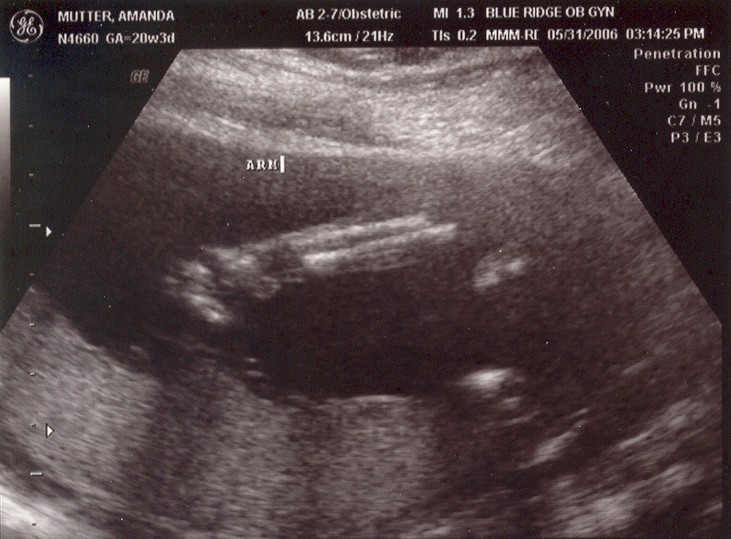

May 31, 2006: Diagnostic Ultrasound

OBs regularly do these to check if babies have all the right number of arms, brains, etc.

It's a girl! After getting this picture, my parents got to stop researching boys' names and circumcision.